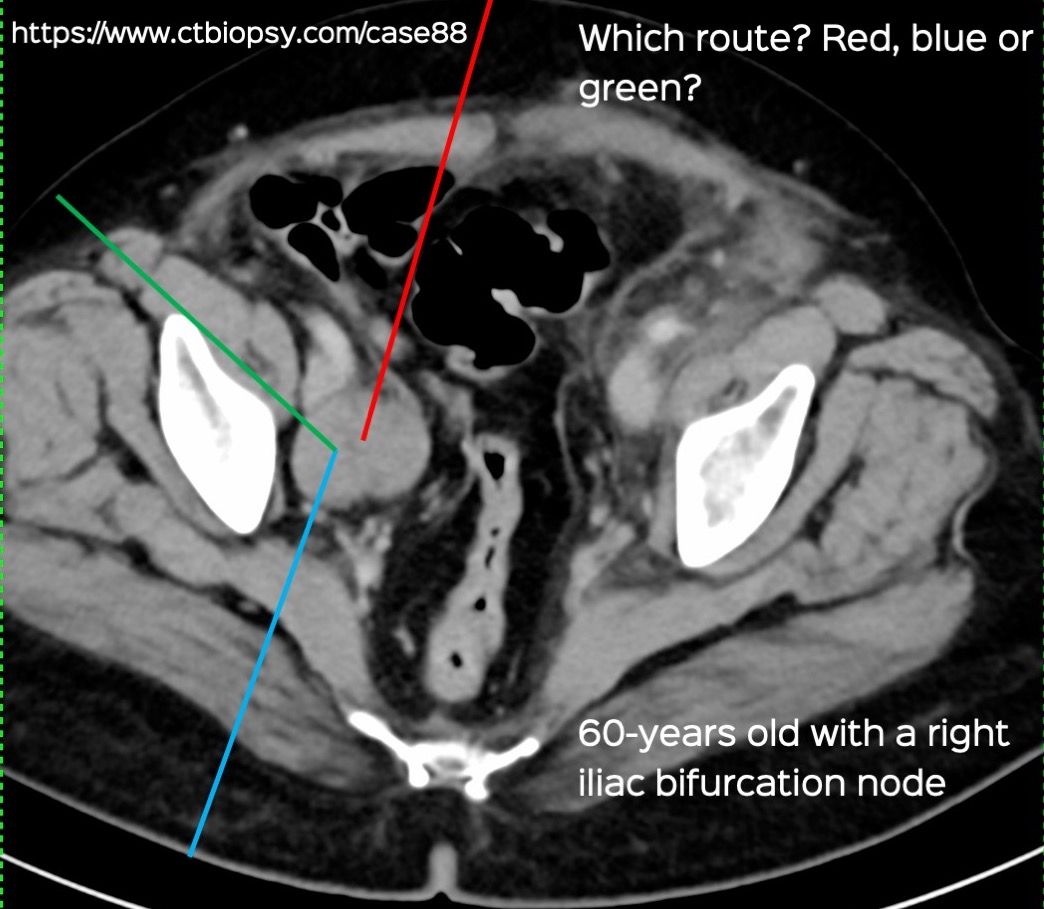

Case 88: Transiliopsoas Route for Iliac Bifurcation Node Biopsy

Bhavin Jankharia - 16 April 2022